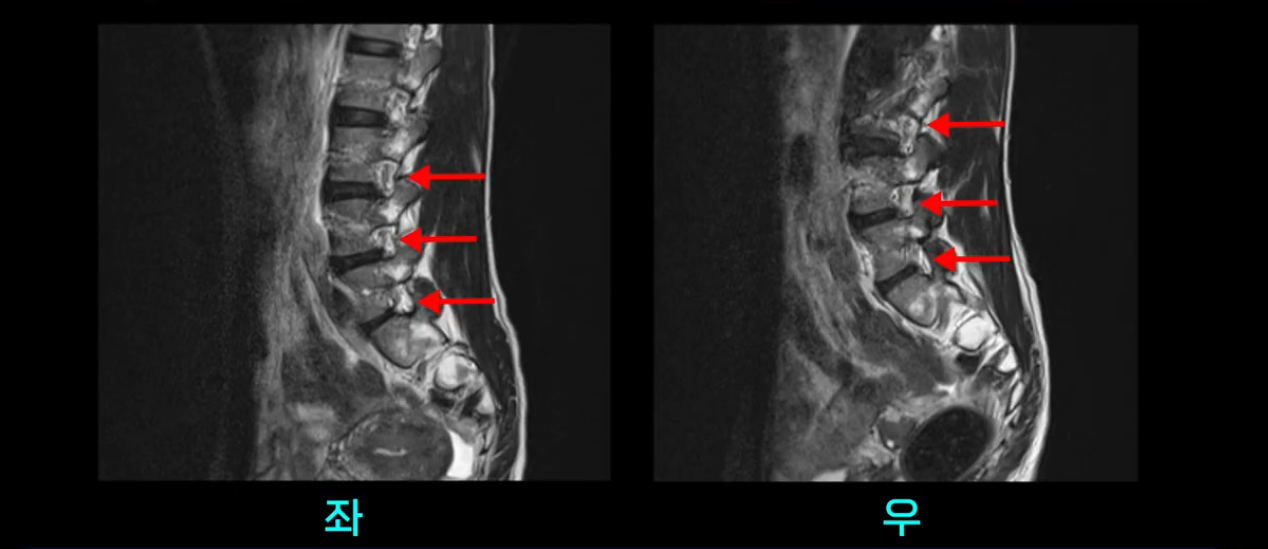

우선 이분의 MRI를 보고 먼저 설명을 드린 후 이런 환자분들의 통증의 원인은 무엇인지, 그리고 치료는 어떻게 해야 하는지 자세히 설명 드리겠습니다.

이분 MRI를 보시면 두 마디의 퇴행성디스크가 있습니다. 그리고 디스크가 조금씩 밀려 나와 있고요. 그런데 디스크 탈출 정도는 두 마디 다 심하지 않습니다. 4번 5번에는 디스크 탈출이 약간 있고,

척추관협착도 약간 진행이 되고 있고요.

5번 1번은 디스크 탈출이 가운데 쪽으로 살짝 있습니다.

또한 양쪽 신경 가지가 빠져나가는 추간공은 매우 넓은 상태입니다.

중요한 것은 이 정도 경미한 탈출과 협착으로는 양쪽 다리가 저리고 아플 수가 없습니다.

그리고 만약에 이 디스크가 급성으로 찢어진 것이라면 아주 심한 디스크성 통증이 있겠죠. 기침이나 재채기를 하면 심하게 아프고 허리를 조금만 구부려도 아주 날카로운 통증들이 생길 겁니다. 그런데 이분은 이런 증상이 전혀 아닙니다. 디스크의 돌출 정도와 협착이 전혀 심하지 않기 때문에 이분이 가지고 계신 양쪽 다리 저림, 특히 이분은 누워있을 때도 양쪽 다리가 저리다고 하는데, 디스크 때문에 그런 증상은 생길 수가 없습니다. 또 이 디스크는 오래된 디스크, 이미 찢어진 섬유륜이 아문 디스크이고, 그러니까 이분은 기침이나 재채기를 못하는 증상이 없는 거죠. 그 다음에 허리를 구부릴 때 뻐근한 증상은 있지만 아주 날카로운 통증은 없습니다.

이분 MRI를 보시면 퇴행성디스크가 있고 약간의 협착이 있지만 이 정도의 퇴행성디스크와 협착으로는 신경이 눌려서 양쪽 다리가 저리고 아픈 증상이 나올 수가 없습니다. 그래서 MRI와 이 환자분의 다리 증상이 매치가 안 된다고 하는 의사들이 많은 겁니다.